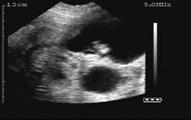

86 days gestation

95 days gestation

85 days of gestation

95 days of gestation